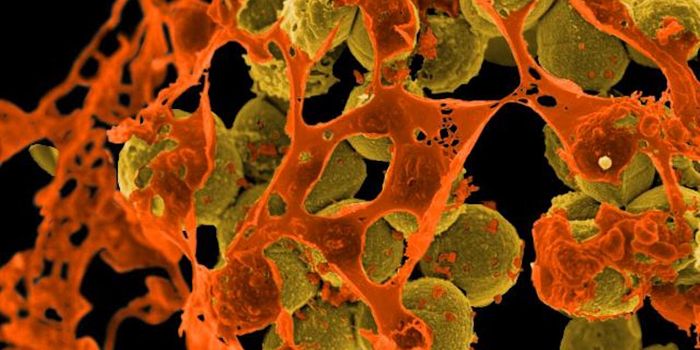

MAR 26, 2024MicrobiologyThere are trillions of microbes in the human gastrointestinal tract, each of which expresses its own genome, and carries ...